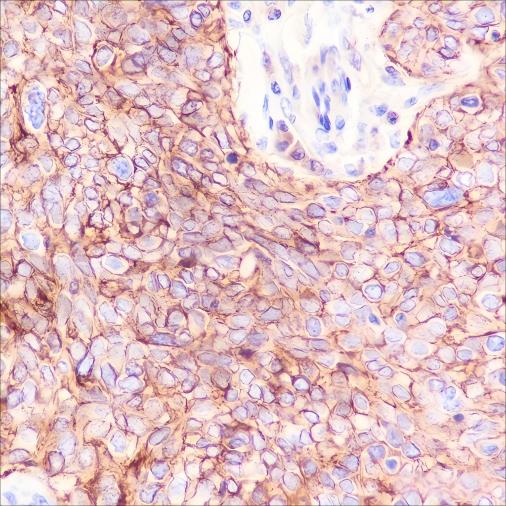

Verified Samples in WB: HeLa, RAW264.7, C6, Mouse brain, Rat brain Verified Samples in IHC: Human cervical cancer, Human kidney Verified Samples in IF: Jurkat, LNCaP |

| Dilution | WB 1:500-1:2000, IHC 1:200-1:1000, IF 1:50 |